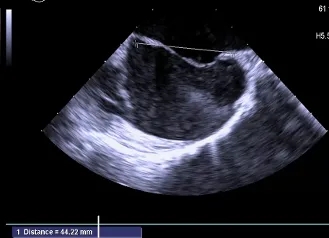

房间隔总长44.22mm,缺损大小14.80mm